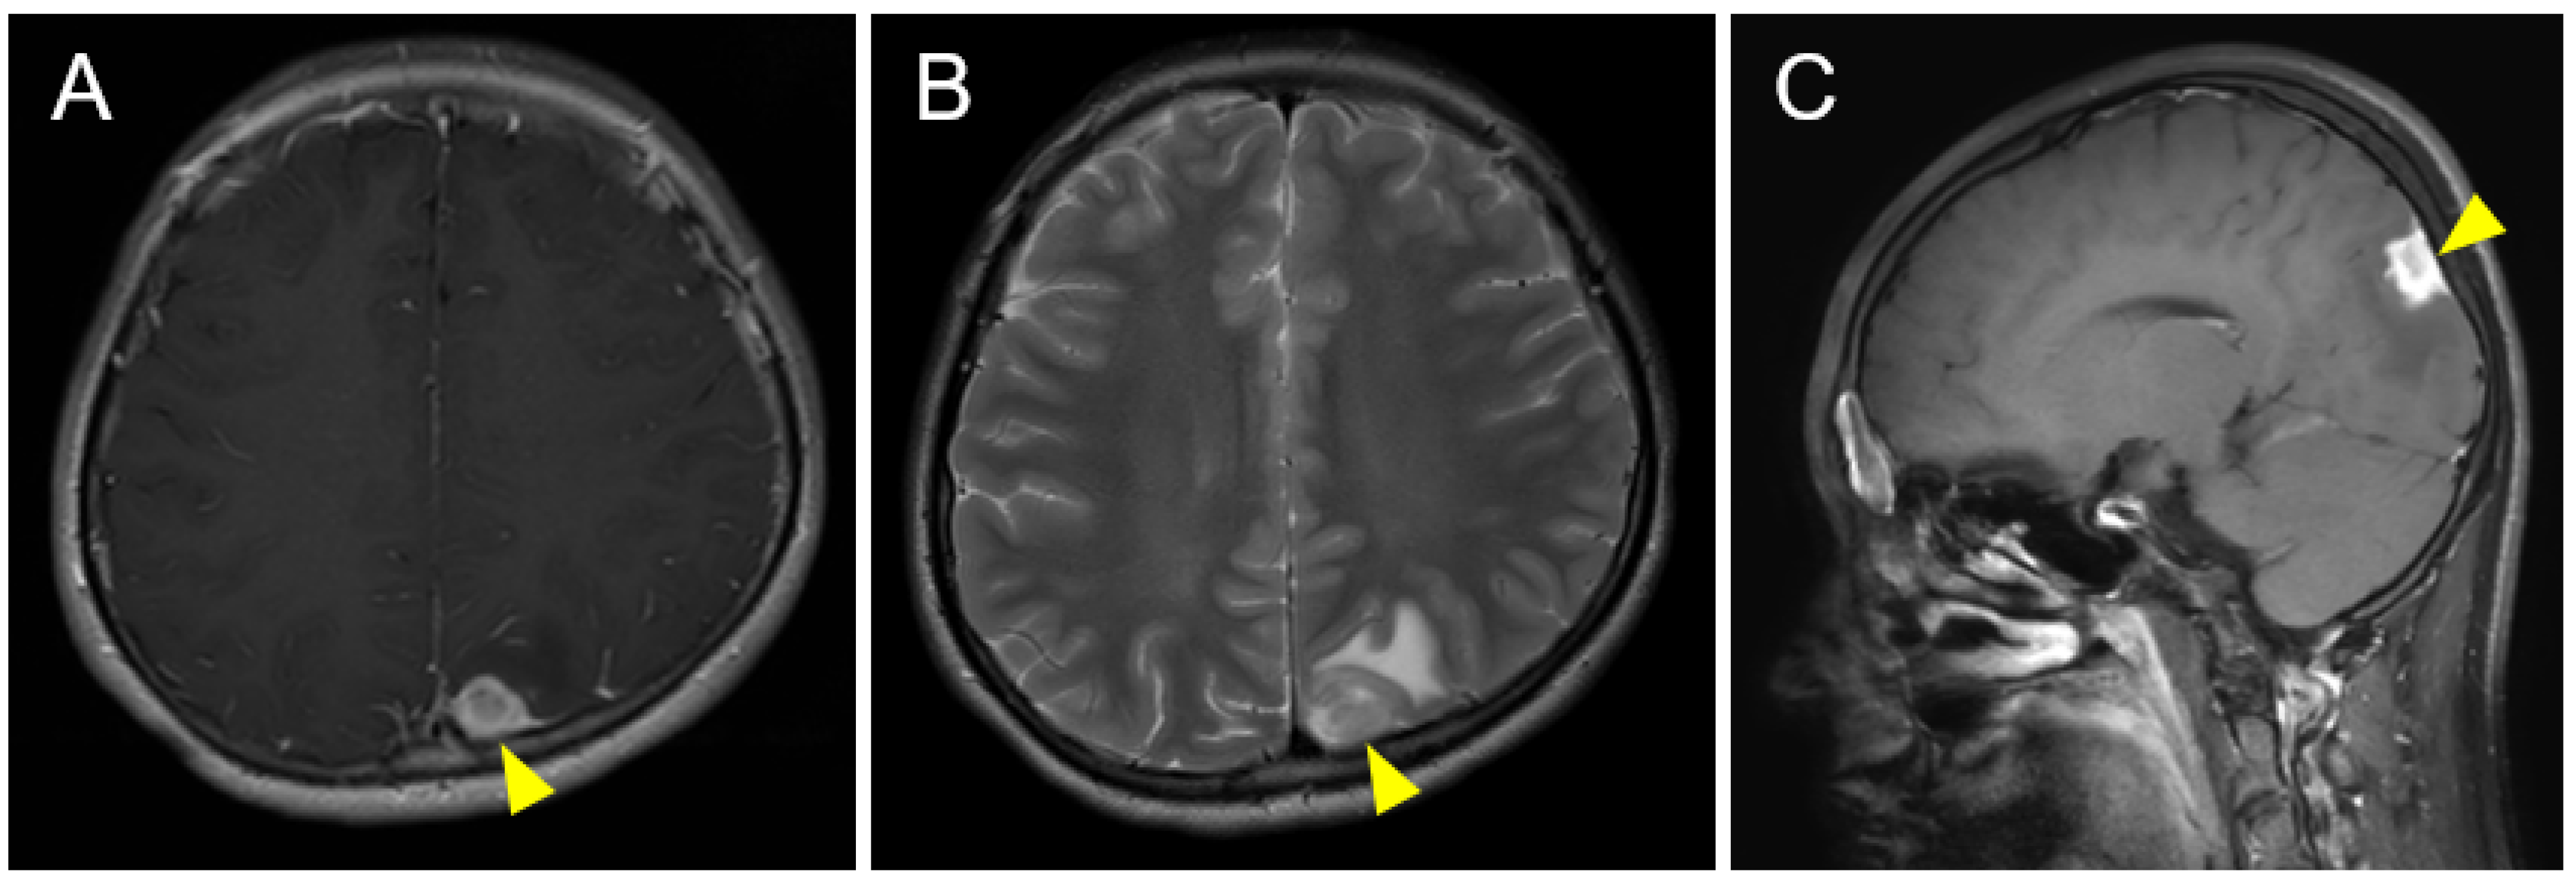

2. Case Description